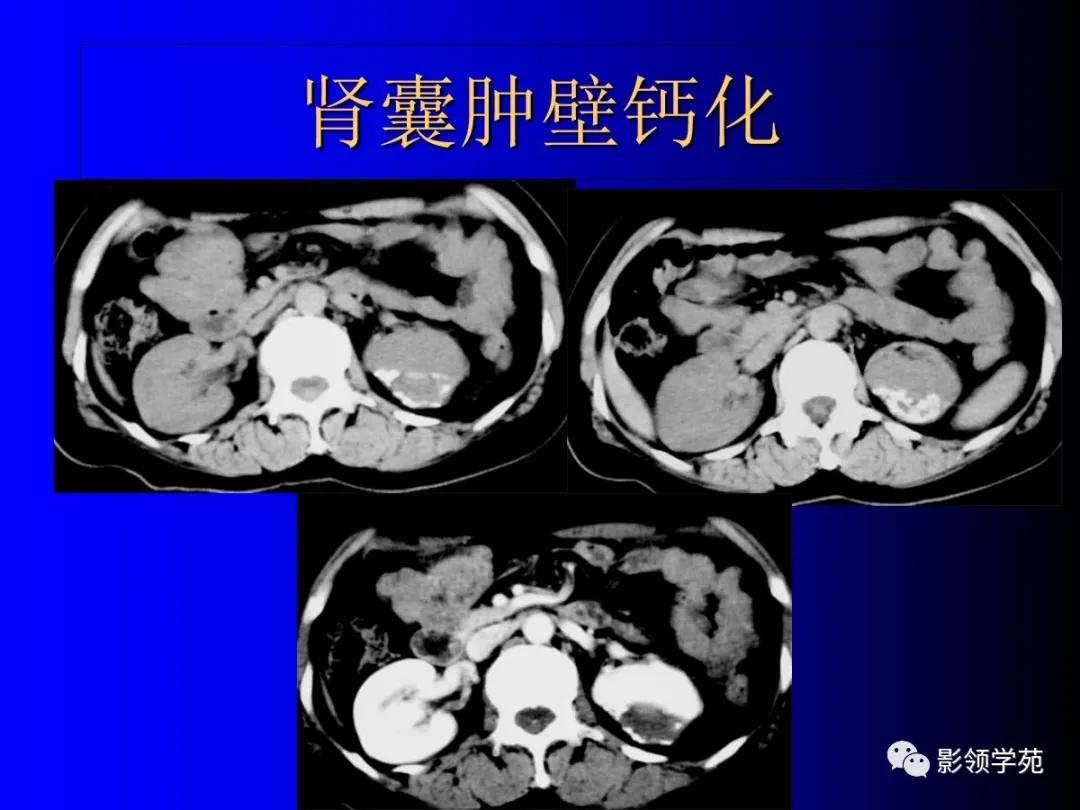

2、复杂性肾囊肿(Complicated cysts)

肾囊肿内含有血液、脓液、间隔或钙化

钙化性囊肿。

明显且不规则钙化

(7)囊壁弥漫弧形钙化,良性单纯囊肿很少见,是否为囊性肾癌的典型征象尚有待商榷。